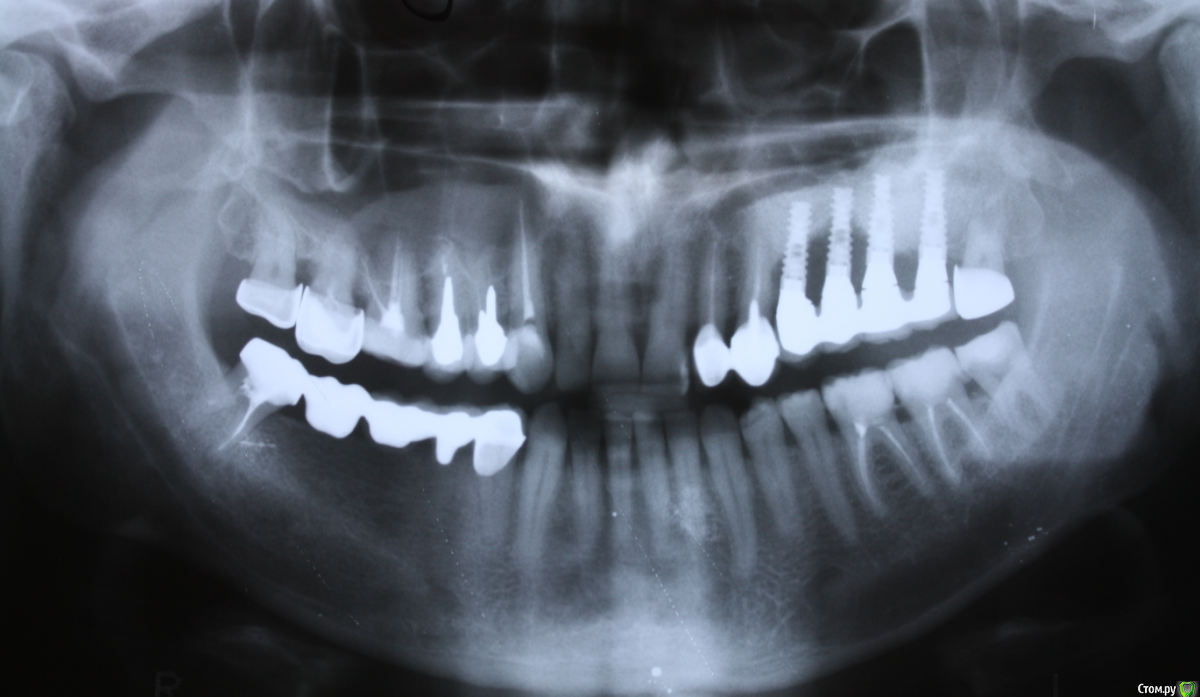

Малик Опубликовано 4 декабря, 2014 Поделиться Опубликовано 4 декабря, 2014 Доброго дня! коллеги,подскажите пожалуйста систему данных имплантатов. Заранее благодарю) Ссылка на комментарий

Военный Врач Опубликовано 4 декабря, 2014 Поделиться Опубликовано 4 декабря, 2014 Израиль как мне кажется... 2 Ссылка на комментарий

Чертков Александр Опубликовано 5 декабря, 2014 Поделиться Опубликовано 5 декабря, 2014 Альфа Био или аналог. Ссылка на комментарий